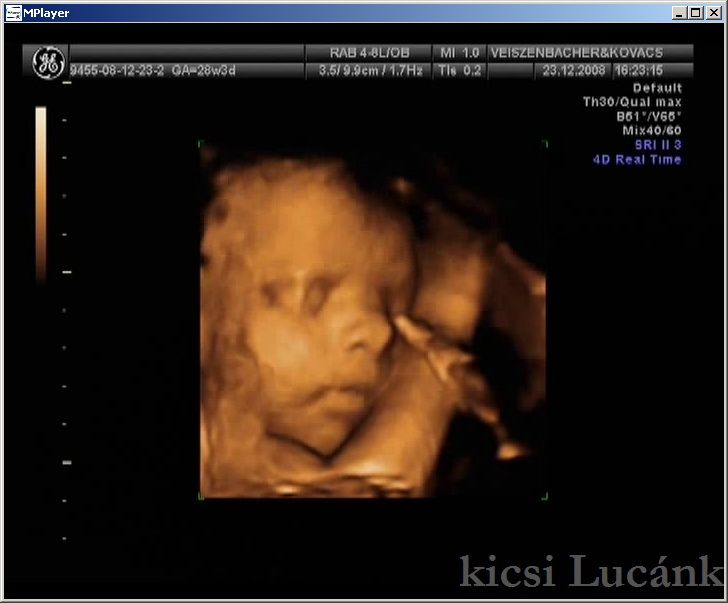

kicsi Lucánk - 2008.12.23 (4 of 13)

luca04